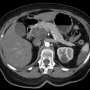

Medical experts are hailing the drug as a potential game-changer. According to recent clinical trial data, patients receiving this treatment have experienced significant tumor shrinkage and prolonged survival, with some living years beyond initial expectations. Doctors stress the importance of this development, as existing treatment options have historically offered limited success.